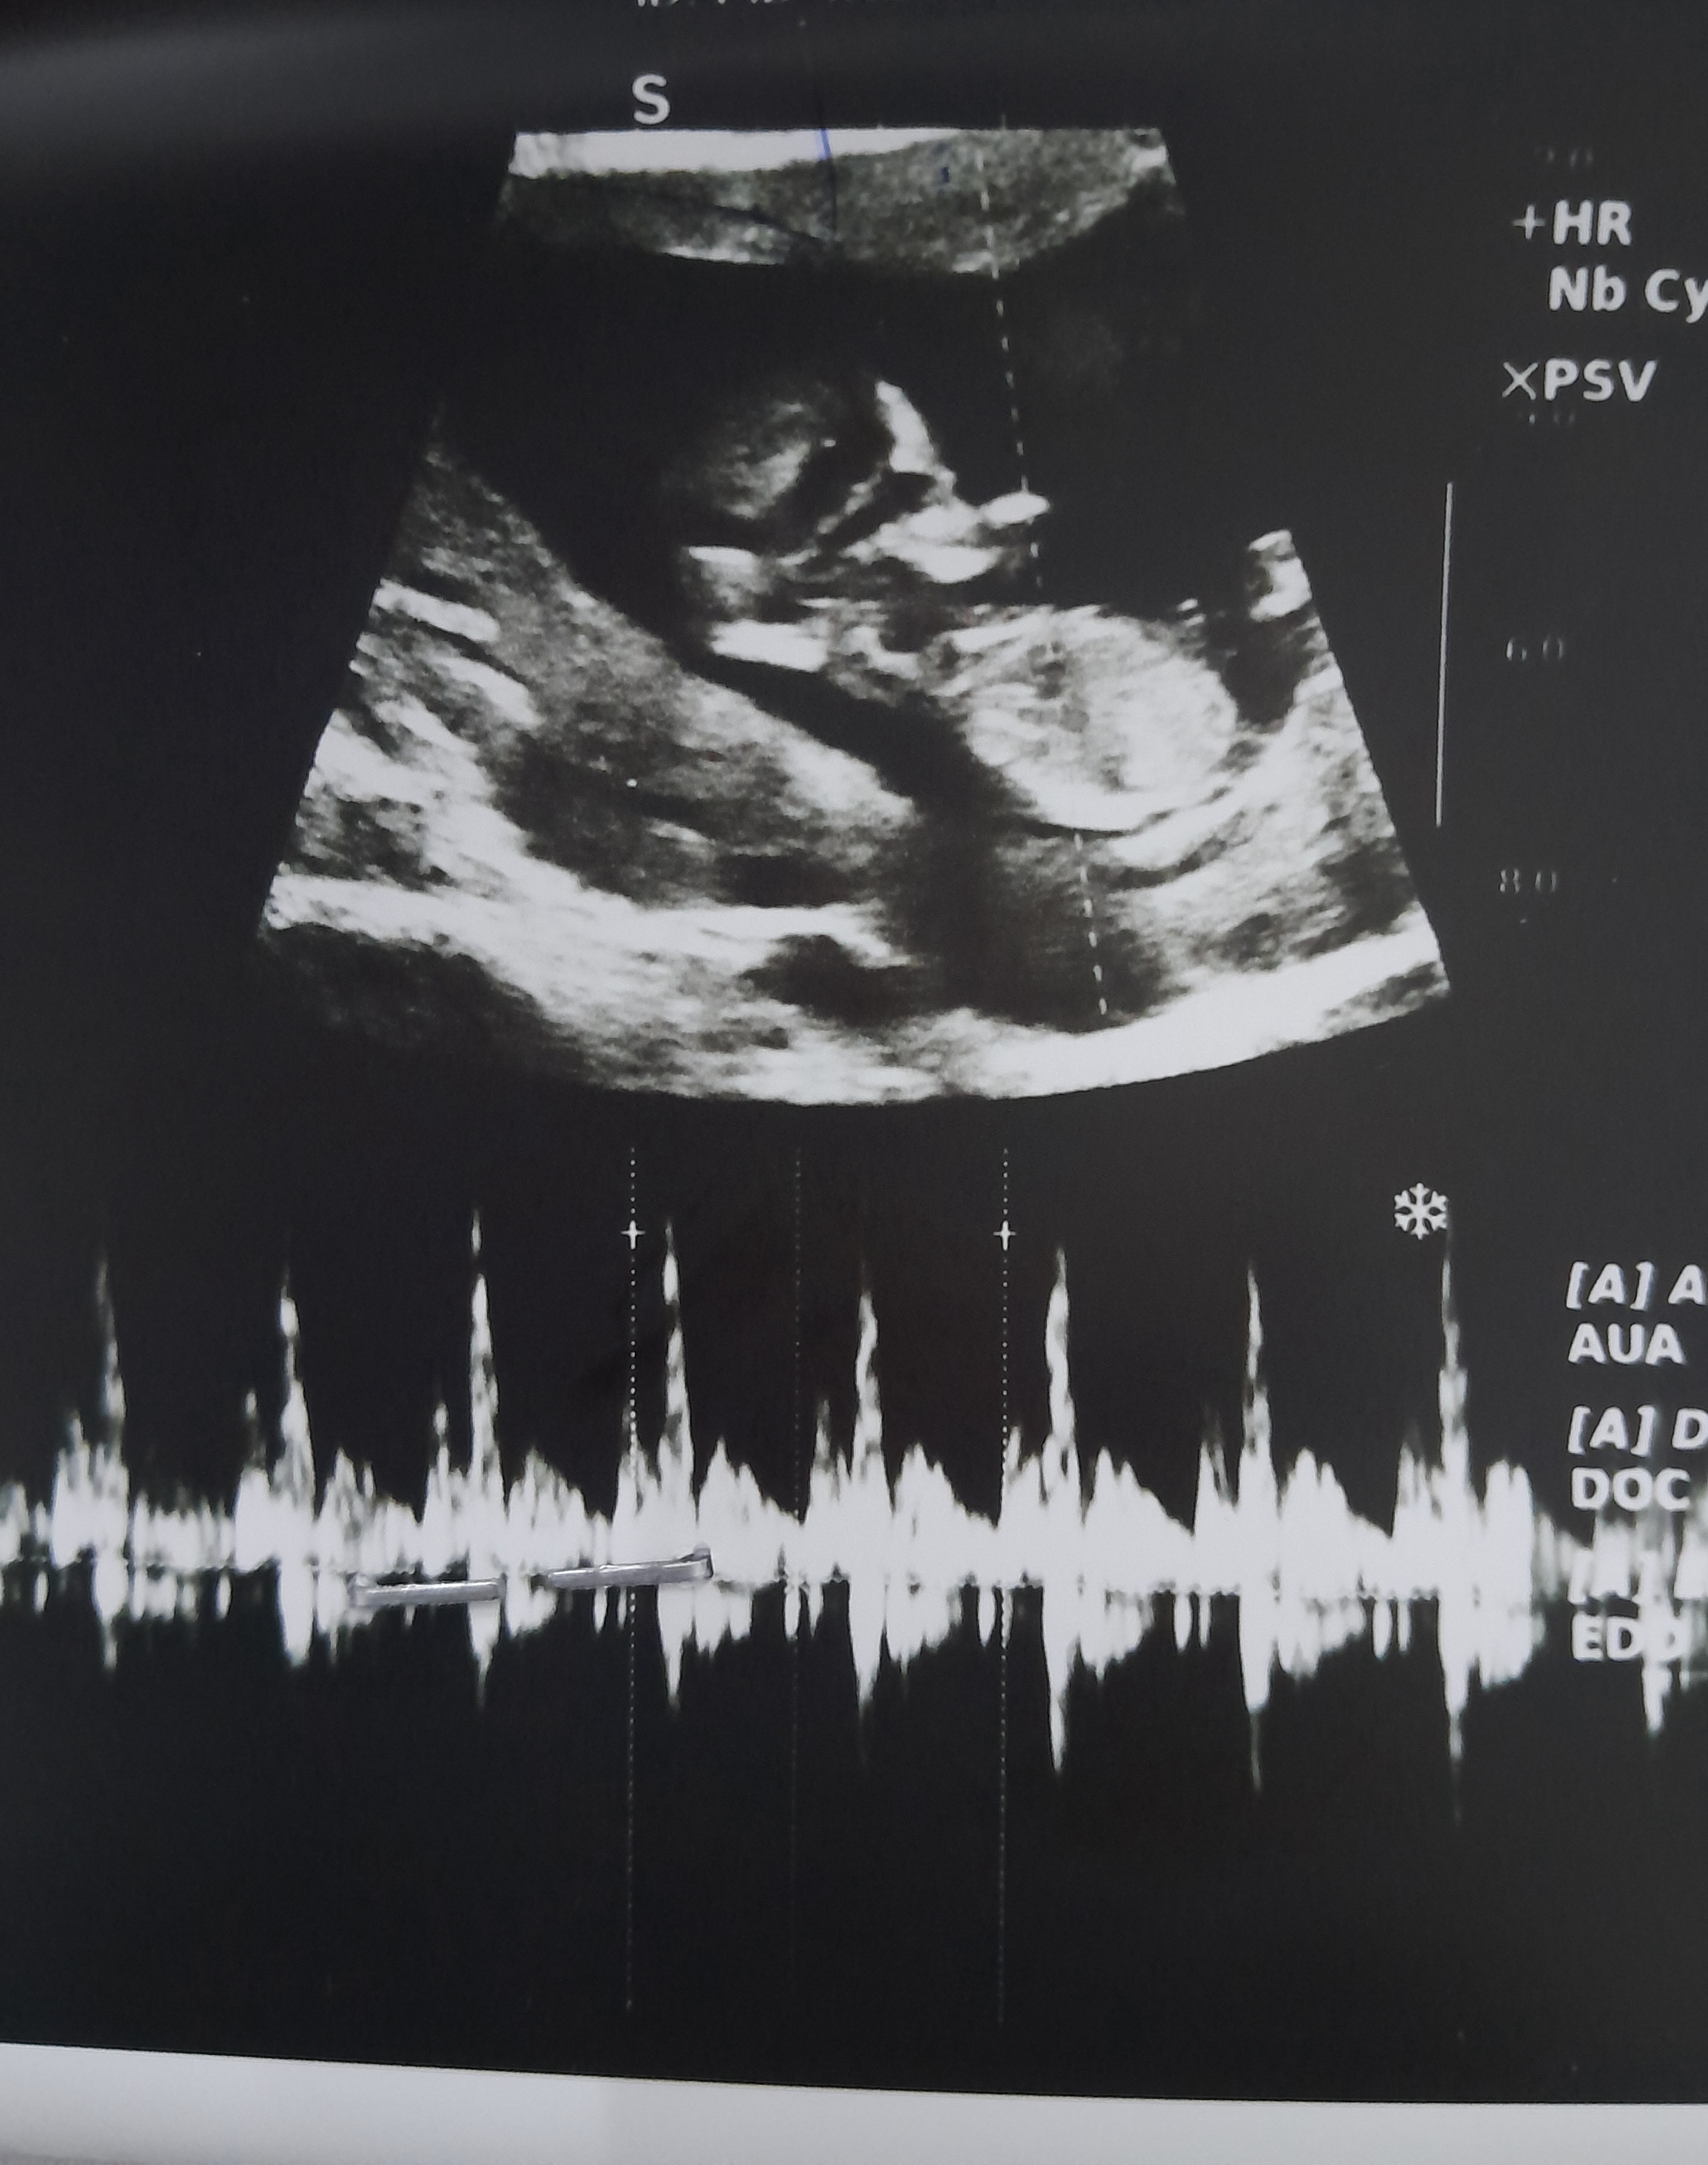

دختر نازم تو ۳۰ هفتگی پرکشیده لطفا برای دلم ی صلوات بفرستین منم براتون صلوات میفرستم ... انشاالله ک همیشه دل خوش باشین. ۱۶.۵.۱۴۰۳